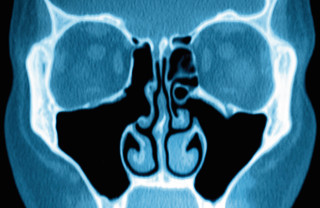

The term sinusitis simply means that the sinuses are inflamed, and this is usually caused by an infection or an allergy.

Normally, mucus drains through small channels into the nose. However, if these channels get blocked, the sinuses can become congested and inflamed.